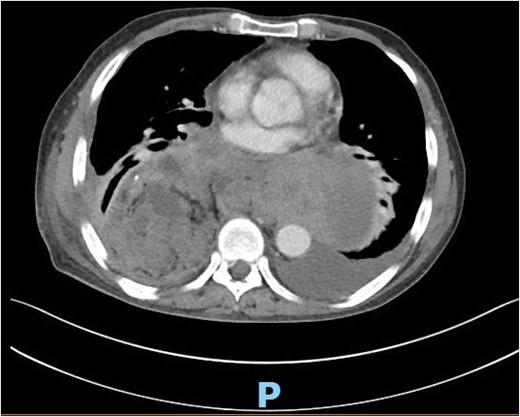

This is a 65-year-old male who was diagnosed with poorly differentiated adenocarcinoma of the esophagus in an outside hospital 4 months prior to his presentation. Endoscopy done previously showed lower esophageal fungating mass that was partially obstructing the lumen. Biopsies taken showed adenocarcinoma. Patient staging work up was negative for metastasis. He received neo-adjuvant chemotherapy and underwent esophagectomy with gastric pull-up 6 weeks before his presentation. He presented to our hospital with a history of progressive shortness of breath, fever, fatigue, loss of appetite, cough, dysphagia, and voice hoarseness. Upon examination, there was a decreased air entry on the right side of the chest with right lung opacity seen on chest X-ray (Fig. 1). CT chest scan showed right posterior mediastinal heterogeneous mass, suggestive of hematoma with pleural thickening (Fig. 2). The patient was booked for right video-assisted thoracoscopic surgery. During the procedure, a right lesion occupying the whole right hemithorax was identified with multiple chest wall nodules, and all were biopsied. After the operation, the patient developed septic shock and eventually went into renal failure, respiratory failure, and cardiac arrest. Patient deceased 24 days after admission.

CT scan of the chest showing right large posterior mediastinal heterogeneous soft tissue mass.